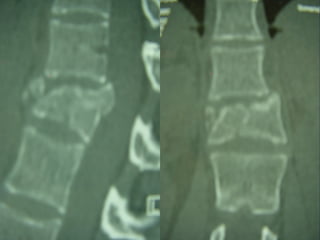

CT - SCAN

3D CT -SCAN

 AANN.. PPEERR..

 FF –– 2222 yyrrss

 FFaallll

 LLeevveell :: TT1122

 TTyyppee :: AA33..33

 AA..SS..II..AA.. :: EE